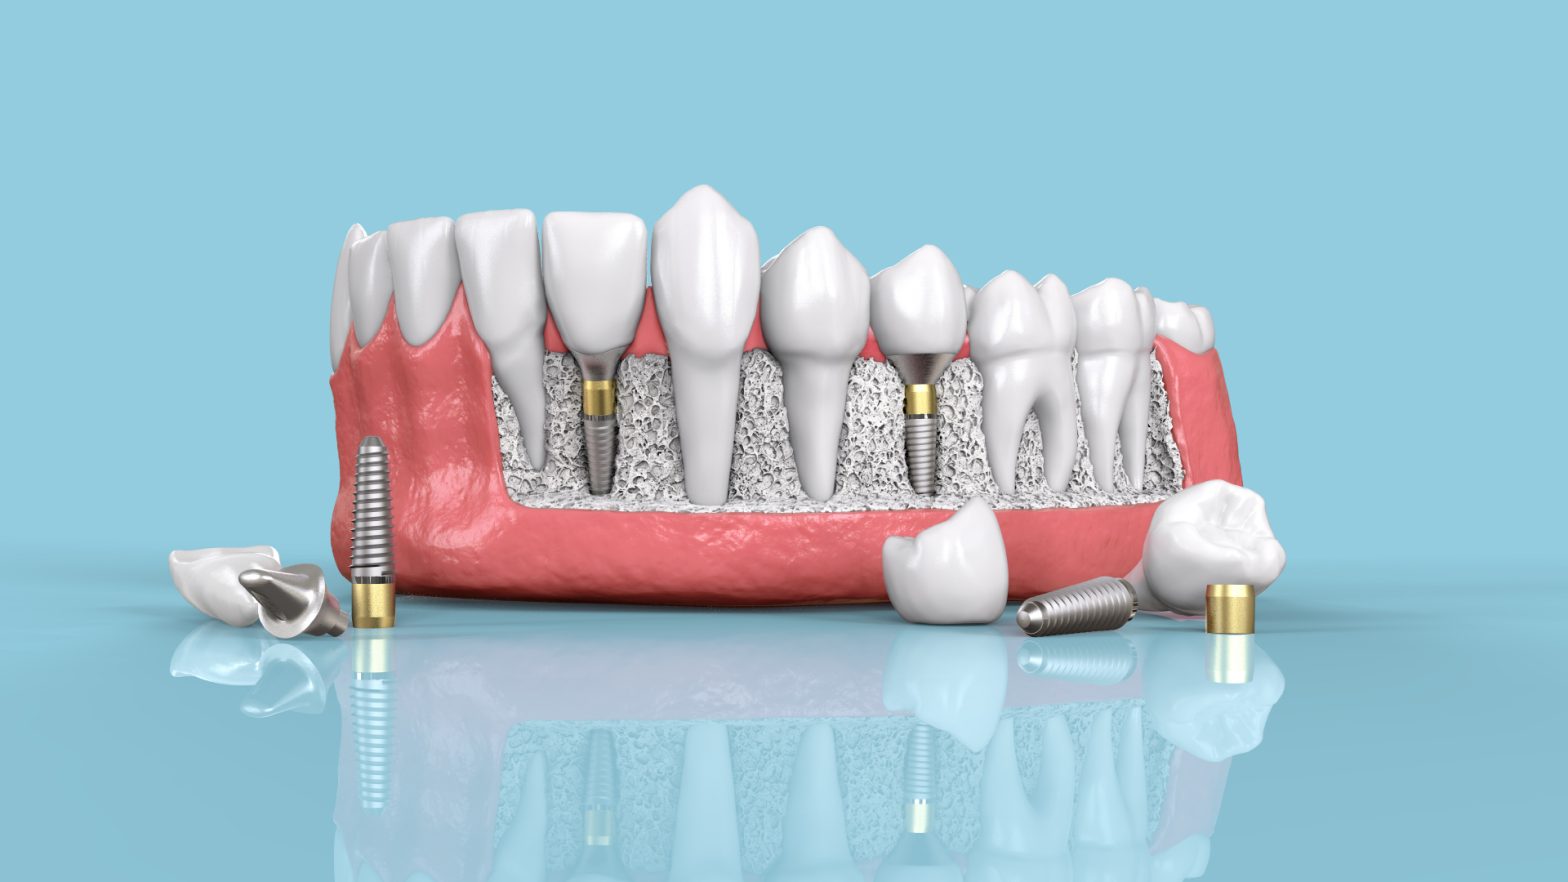

L’implantologie dentaire offre une solution pour remplacer les dents manquantes ou endommagées. L’article explique les éléments essentiels à considérer pour choisir un implant dentaire adapté à vos besoins.

Les implants sont disponibles sous forme de vis cylindriques ou coniques, avec différentes longueurs et diamètres. Les implants cylindriques sont adaptés aux zones à densité osseuse élevée, tandis que les implants coniques sont plus polyvalents et offrent une stabilité accrue.

Les deux principaux matériaux utilisés sont le titane et la zircone. Le titane est couramment utilisé en raison de sa biocompatibilité et de sa fiabilité. La zircone est esthétiquement plus attrayante mais moins éprouvée.

Les implants dentaires sont reliés à une couronne prothétique par le biais de différents types de connexions, telles que les connexions externes ou internes. La connexion interne est devenue plus courante grâce aux avancées technologiques.

Le processus de pose d’un implant comprend la pose proprement dite, l’intégration de l’implant dans l’os et la réalisation de la couronne dentaire artificielle. Chaque étape nécessite une planification minutieuse et des contrôles réguliers.

Les dimensions de l’implant dépendent de la morphologie de la mâchoire et de l’emplacement de la dent à remplacer. Les implants varient en longueur et en diamètre, avec des plateformes larges pour les molaires et des plateformes standards pour les dents de devant.

En résumé, choisir un implant dentaire approprié nécessite de prendre en compte la forme, le matériau, les connexions, les étapes de la pose, les dimensions et les risques potentiels. Une consultation avec un professionnel de la santé dentaire est essentielle pour déterminer la meilleure option pour votre situation particulière.